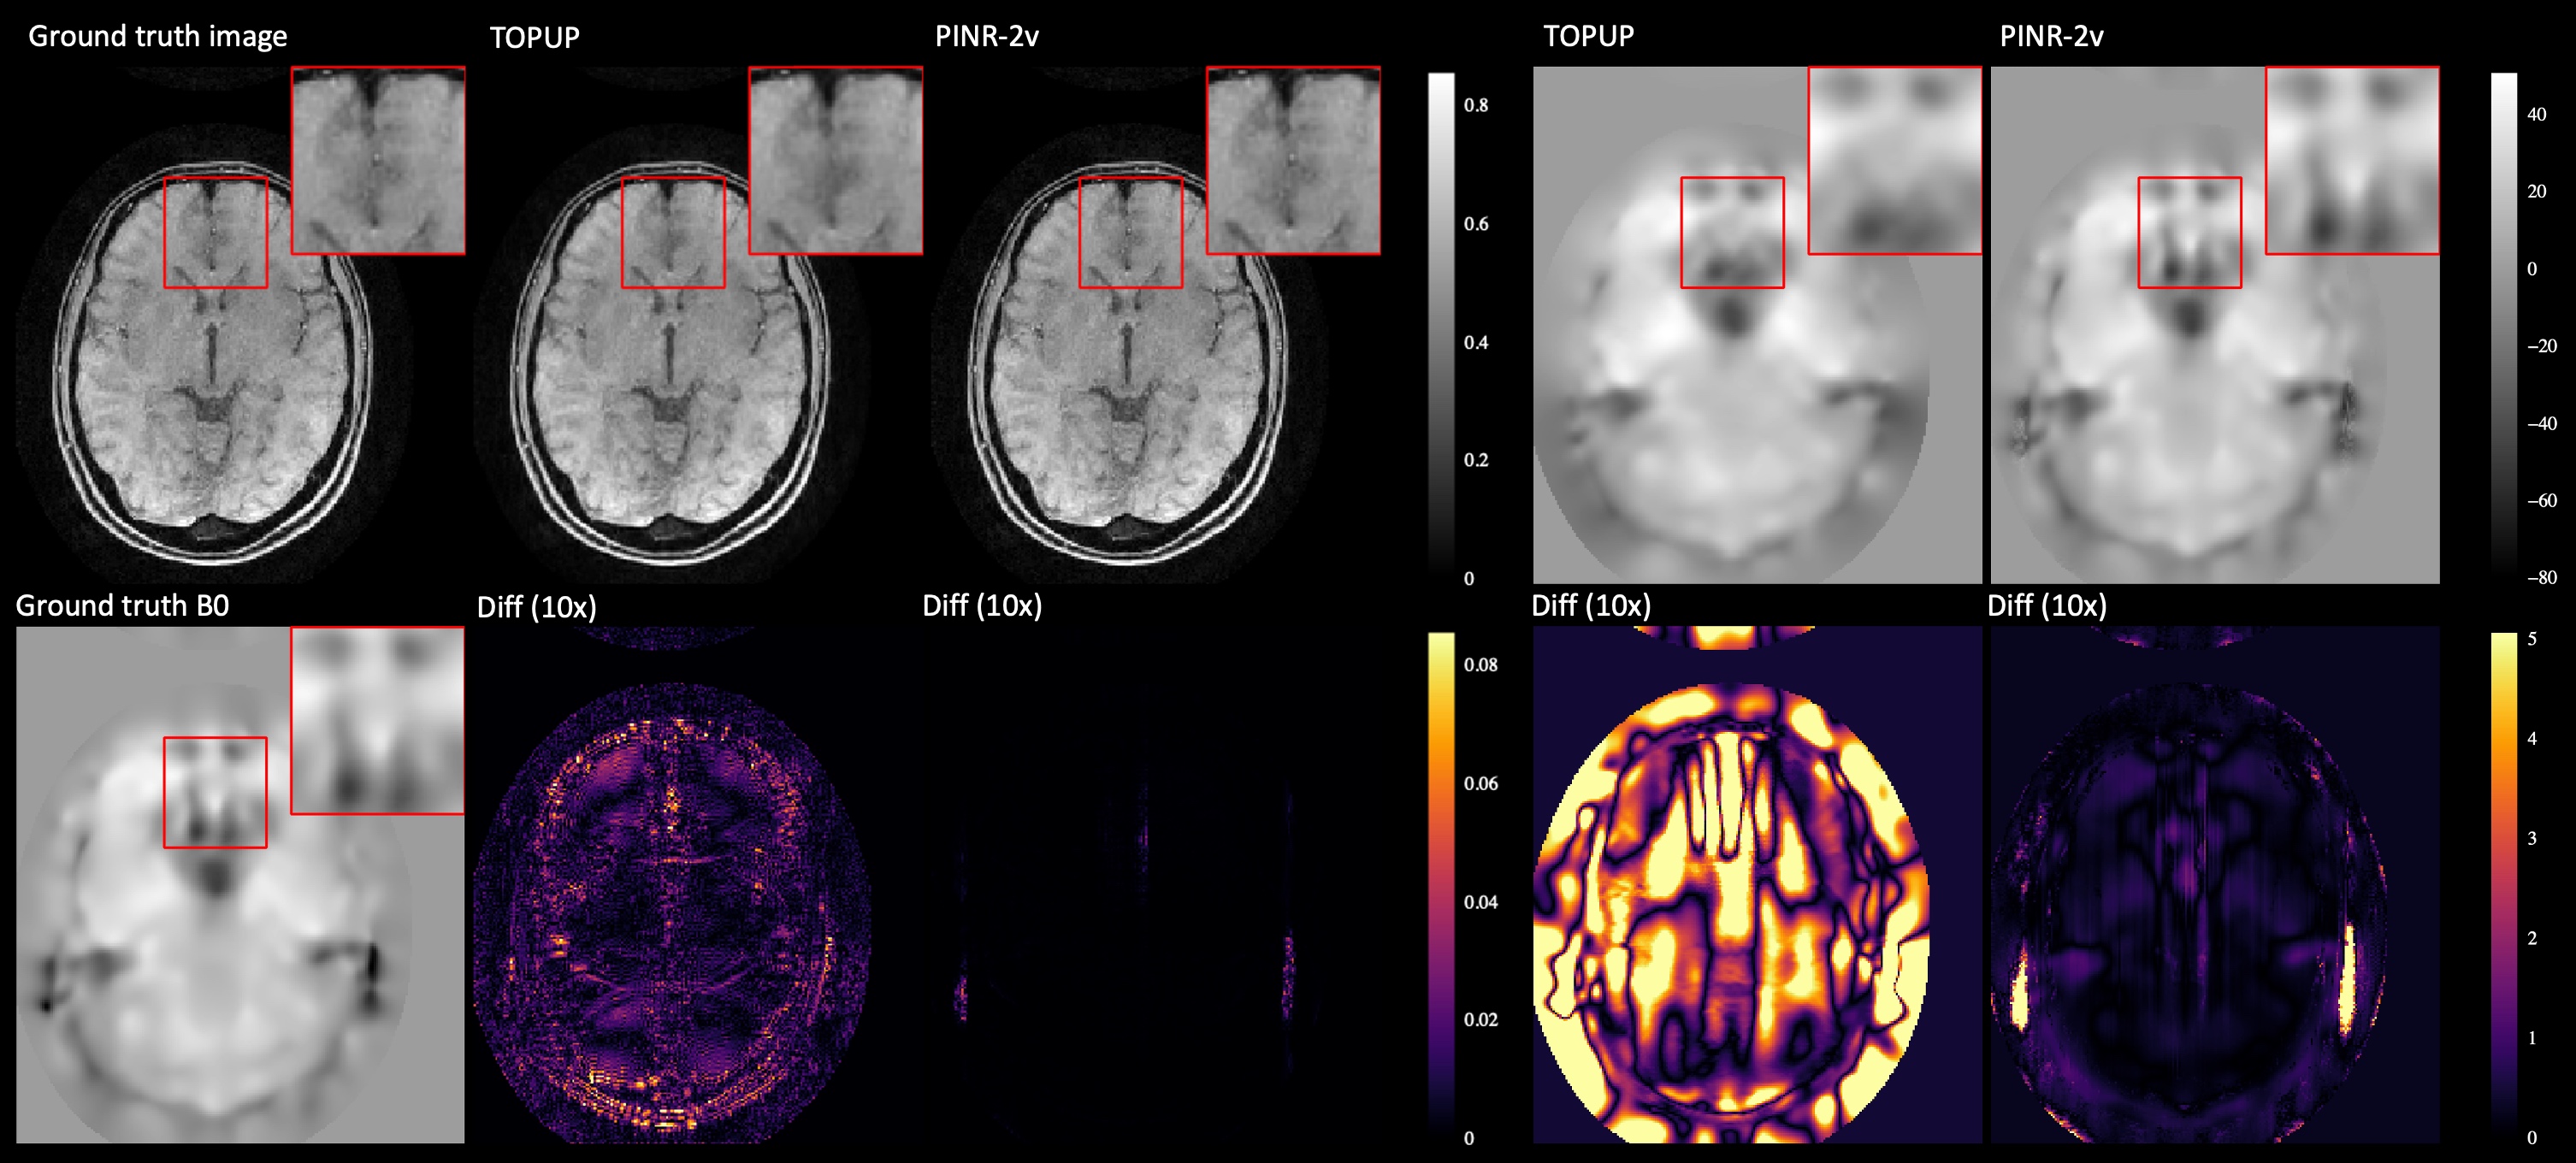

Refer to caption

Figure 2: Comparison with two-view (blip-up/down) acquisition. The first column shows the ground truth image and B0 field. The second and third columns present TOPUP-corrected results and our method’s results, along with their error maps. The right two columns display B0 estimates from TOPUP and our method, with corresponding error maps below. The red box highlights the zoomed-in region of interest (ROI).

Figure 2 compares TOPUP and our two-view PINR. The ROI shows that TOPUP produces blurrier images, while PINR preserves finer structures. Error maps reveal residual aliasing in TOPUP, likely from GRAPPA reconstruction errors. Since TOPUP operates in the image domain with separate reconstruction and B0 correction steps, errors in distorted EPI propagate into B0 estimation, degrading the final image. PINR consistently achieves lower B0 error, particularly in the ROI, benefiting from INRs’ flexibility and joint optimization. In contrast, TOPUP’s Gaussian-based B0 estimation oversmooths high-susceptibility regions. These results highlight the advantage of our joint framework for precise B0 estimation and distortion correction.